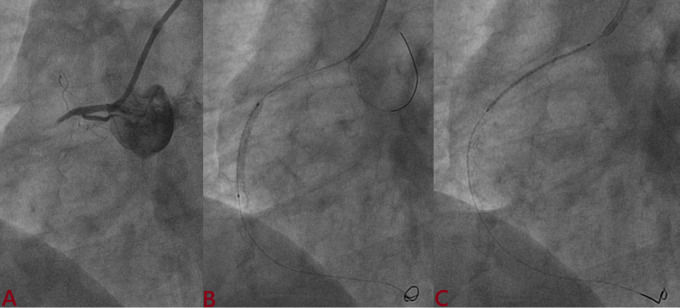

Background: Intravascular ultrasound (IVUS)-guided percutaneous coronary intervention (PCI) is useful for stent optimization. Outcomes of the ultrathin Supralimus Tetriflex stent (Sahajanand Medical Technologies Pvt. Ltd., India) using IVUS were evaluated among patients with short (≤ 20 mm) versus long lesions (≥ 20 mm).

Methods: A total of 207 patients underwent PCI, and IVUS was performed post-deployment. The primary outcome was optimal stent deployment, defined as (a) mean surface area (MSA) >5.0 mm²; (b) plaque burden <50%; (c) complete apposition; and (d) no edge dissection. Secondary outcomes were target lesion failure (TLF)-a composite of cardiac death, target vessel myocardial infarction (TVMI), and target lesion revascularization (TLR)-stent thrombosis, and major adverse cardiovascular events (MACE; a composite of death, MI, stent thrombosis, and repeat revascularization).

Results: Suboptimal deployment was significantly more frequent among patients with longer lesions (30.1% vs. 23.3%; p=0.03) due to higher rates of malapposition (17.3% vs. 10.6%) and MSA <5 mm² (9.6% vs. 7.7%). Following post-dilatation, suboptimal deployment was observed in 7.6% and 5.8% of patients, respectively. Residual plaque burden was 4.5% and 5.7%, respectively. The MSA in both groups was 6.3 mm² and 6.5 mm². Minimum and mean stent expansions were 82.1% versus 81.7% and 106.3% versus 109.8%, respectively, with no significant differences. TLF and stent thrombosis were observed in 0.9% versus 0.9% and 2.9% versus 3.8% of patients, respectively, with no significant differences. However, MACE was significantly higher (10.5% vs. 8.7%; p=0.05) among patients with longer lesions.

Conclusion: Supralimus Tetriflex stent has very good optimal deployment based on angiogram and becomes better with IVUS imaging, making it safe among long lesions (≥ 20mm).